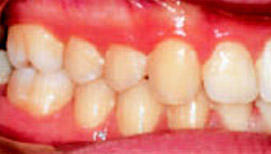

Рис.5: Через 3 дня после начала лечения

В процессе лечение в результате одновременного перемещения зубов – протрудирование верхних и ретрудирование нижних резцов – нормализация смыкания зубов достигается за очень короткое время. Даже при врожденной патологии достаточно обычного режима ношения аппарата - всего два часа днем и всю ночь.